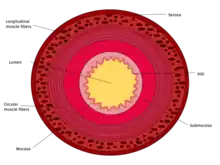

The three sections of the small intestine look similar to each other at a microscopic level, but there are some important differences. The parts of the intestine are as follows:

Tissue layers (mucosa, submucosa & muscularis)